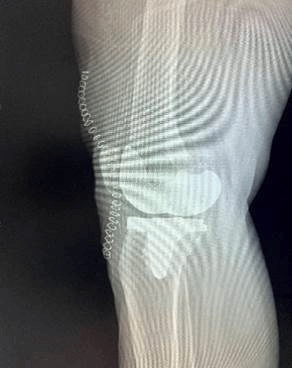

(图六)术后患者X光影相